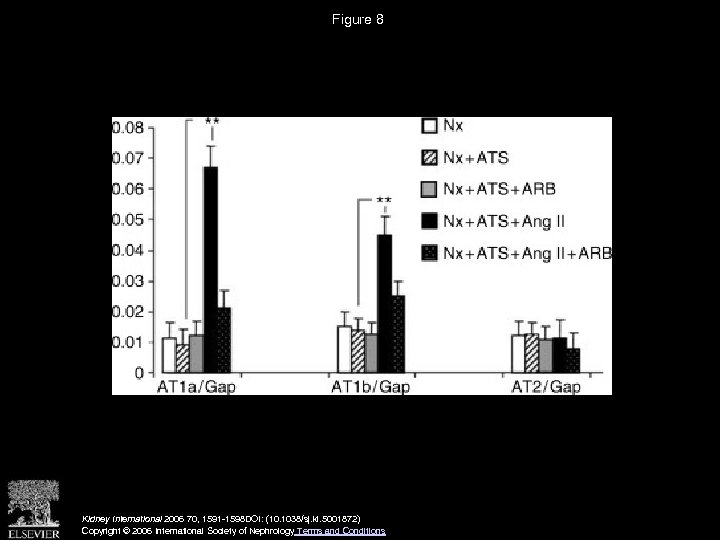

Figure 8 Kidney International 2006 70, 1591 -1598 DOI: (10. 1038/sj. ki. 5001872) Copyright © 2006 International Society of Nephrology Terms and Conditions